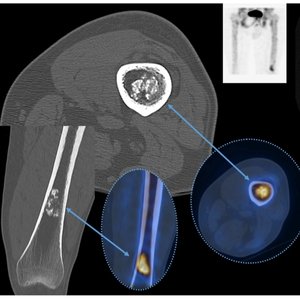

Tumor Ablation

Tumor ablation is a minimally invasive option used to destroy tumors without open surgery. It is commonly used when precise local treatment is needed with faster recovery and organ preservation. Ablation helps control tumor progression, reduce pain, and improve quality of life, especially in patients requiring targeted therapy.